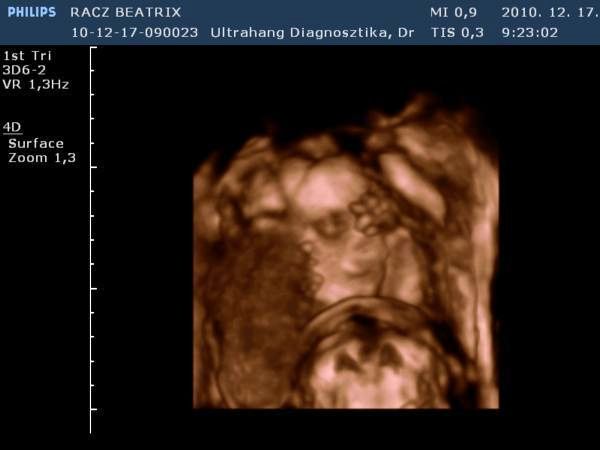

Gyorsan növöget az egyszemkénk, remélem lassan megtudjuk a nemét is! Afp-re dec. 27-én megyek. Az "A" baba még mindig ott van a hegemen és már úgy néz ki ott is marad, majd elnyomja a "B" baba mikor már nagyobb lesz kb a 18-20. héten. De van olyan is akinek szülést követően a méhlepényén találják meg mint egy freskót rajta. Teljesen ott lesz a lenyomata. Majd meglátjuk mi lesz...